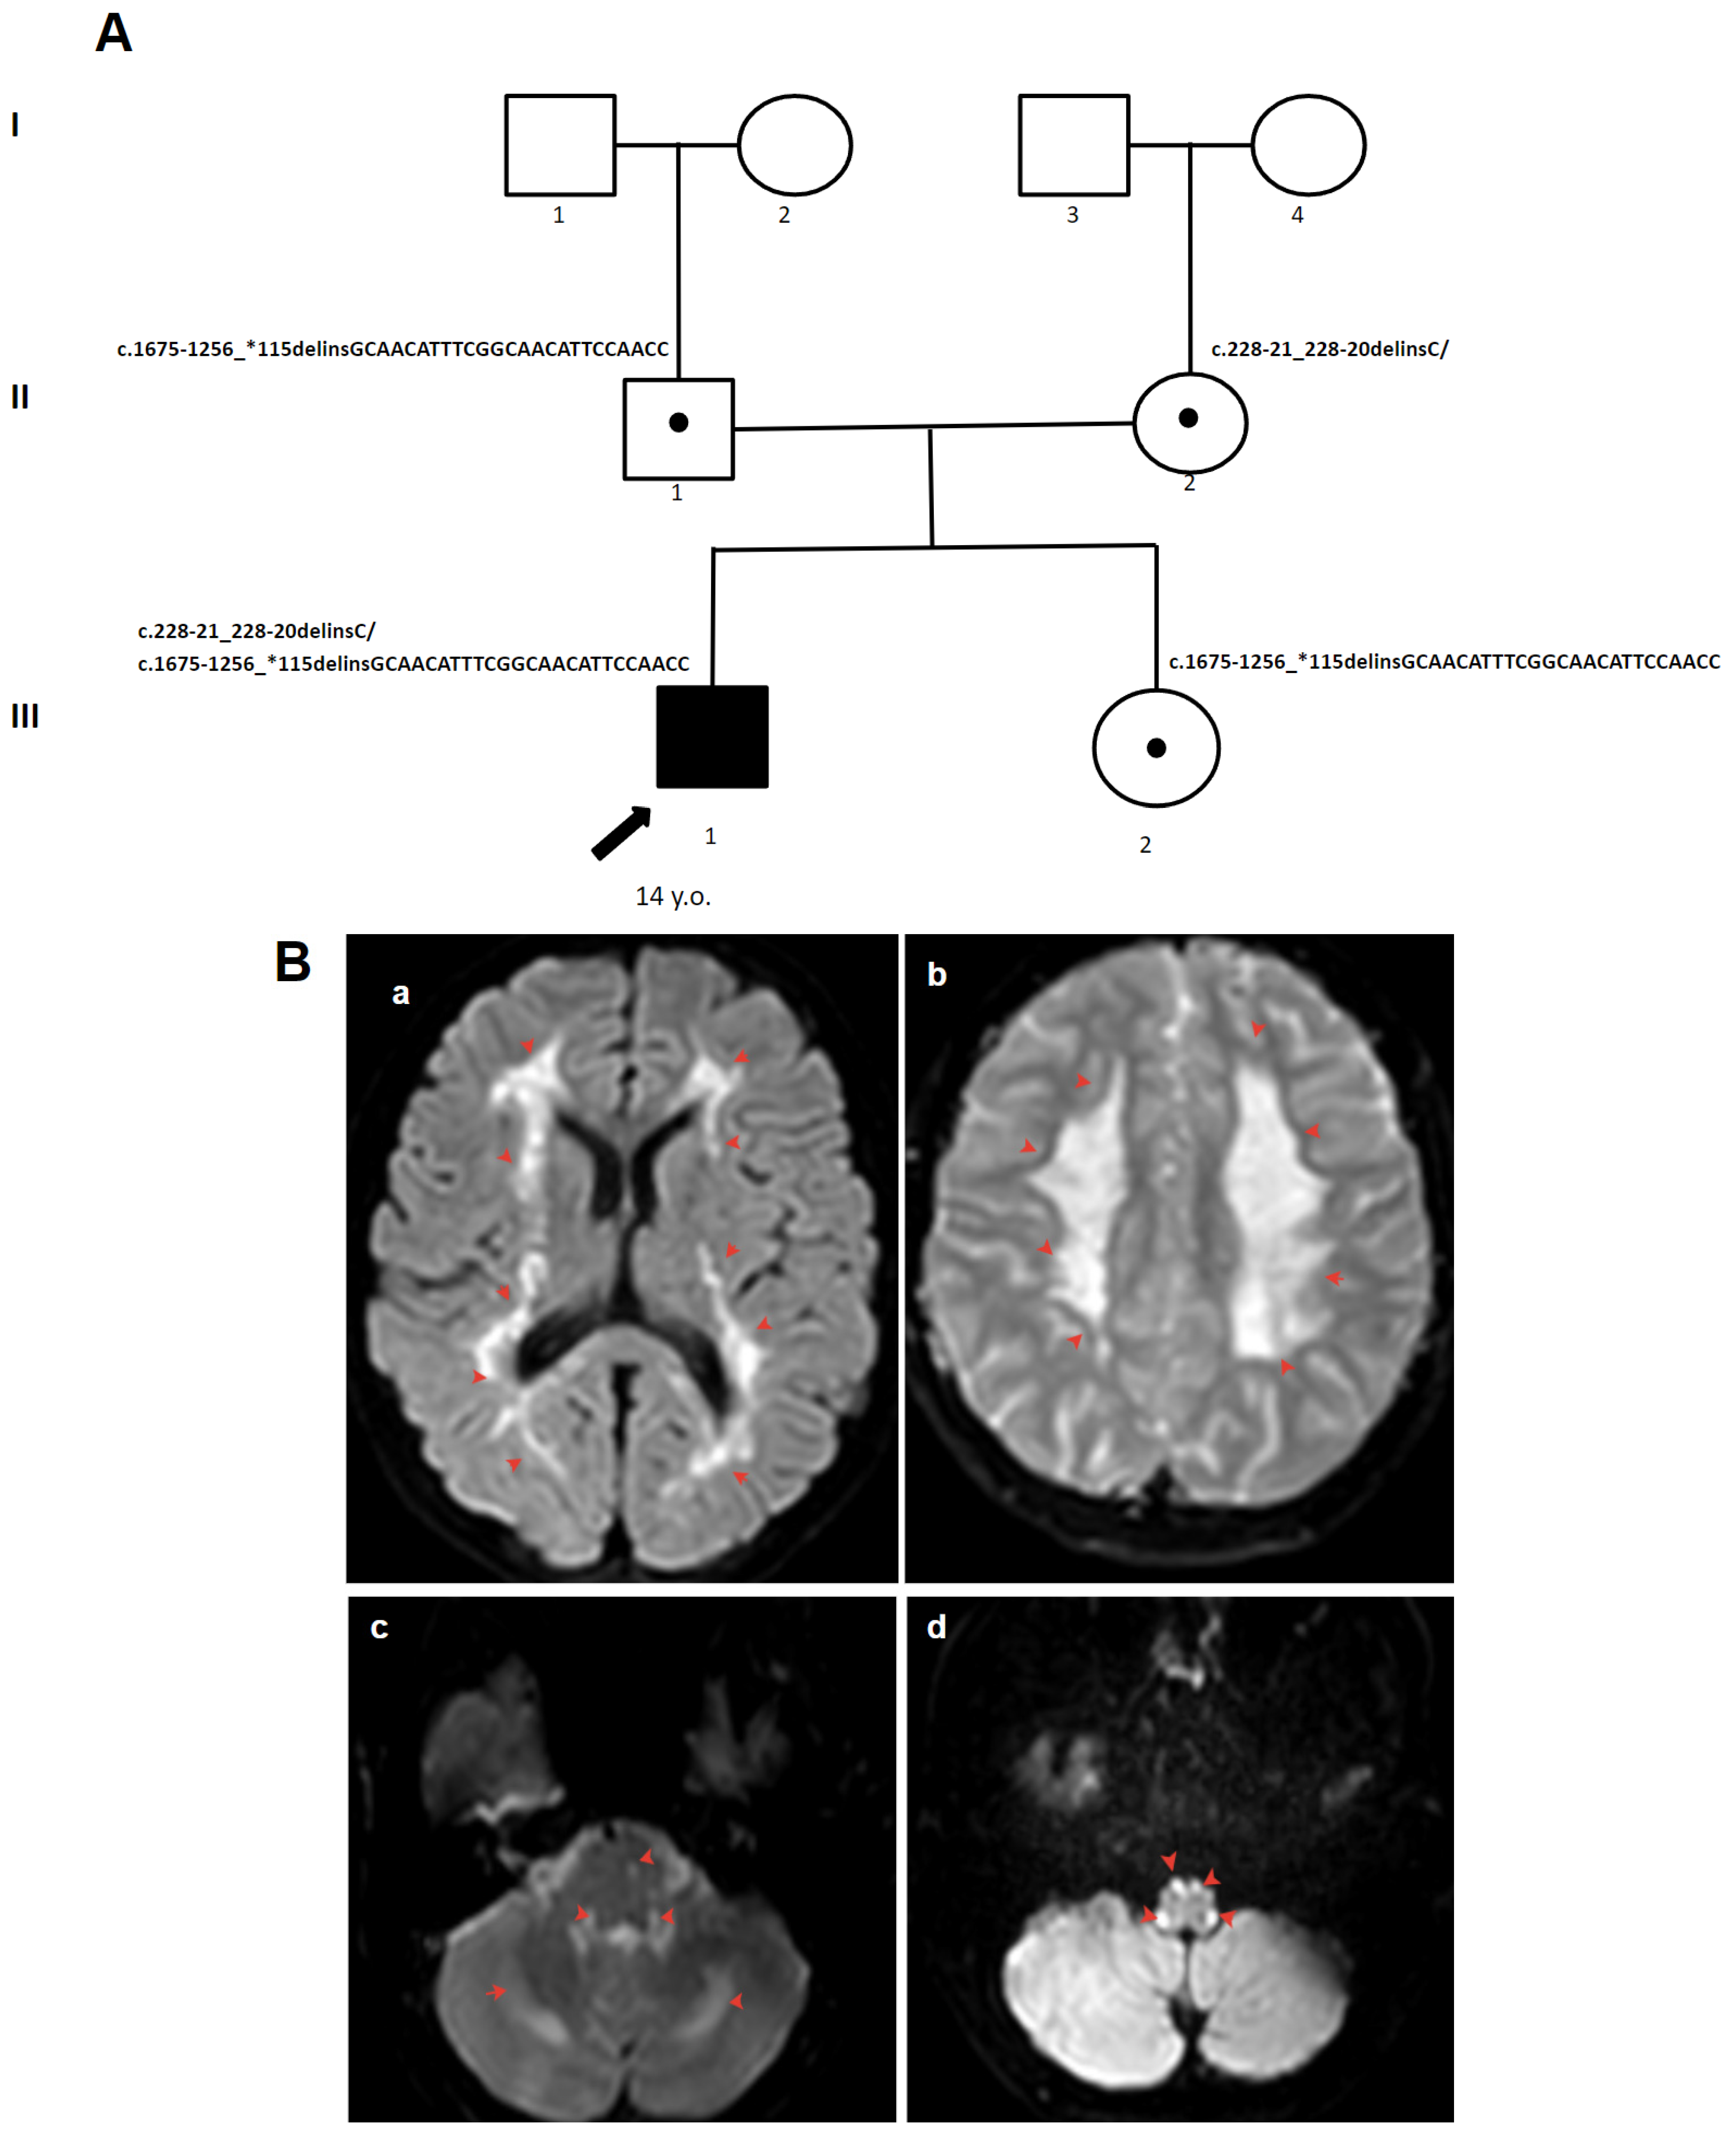

3.1.2. Patient 2